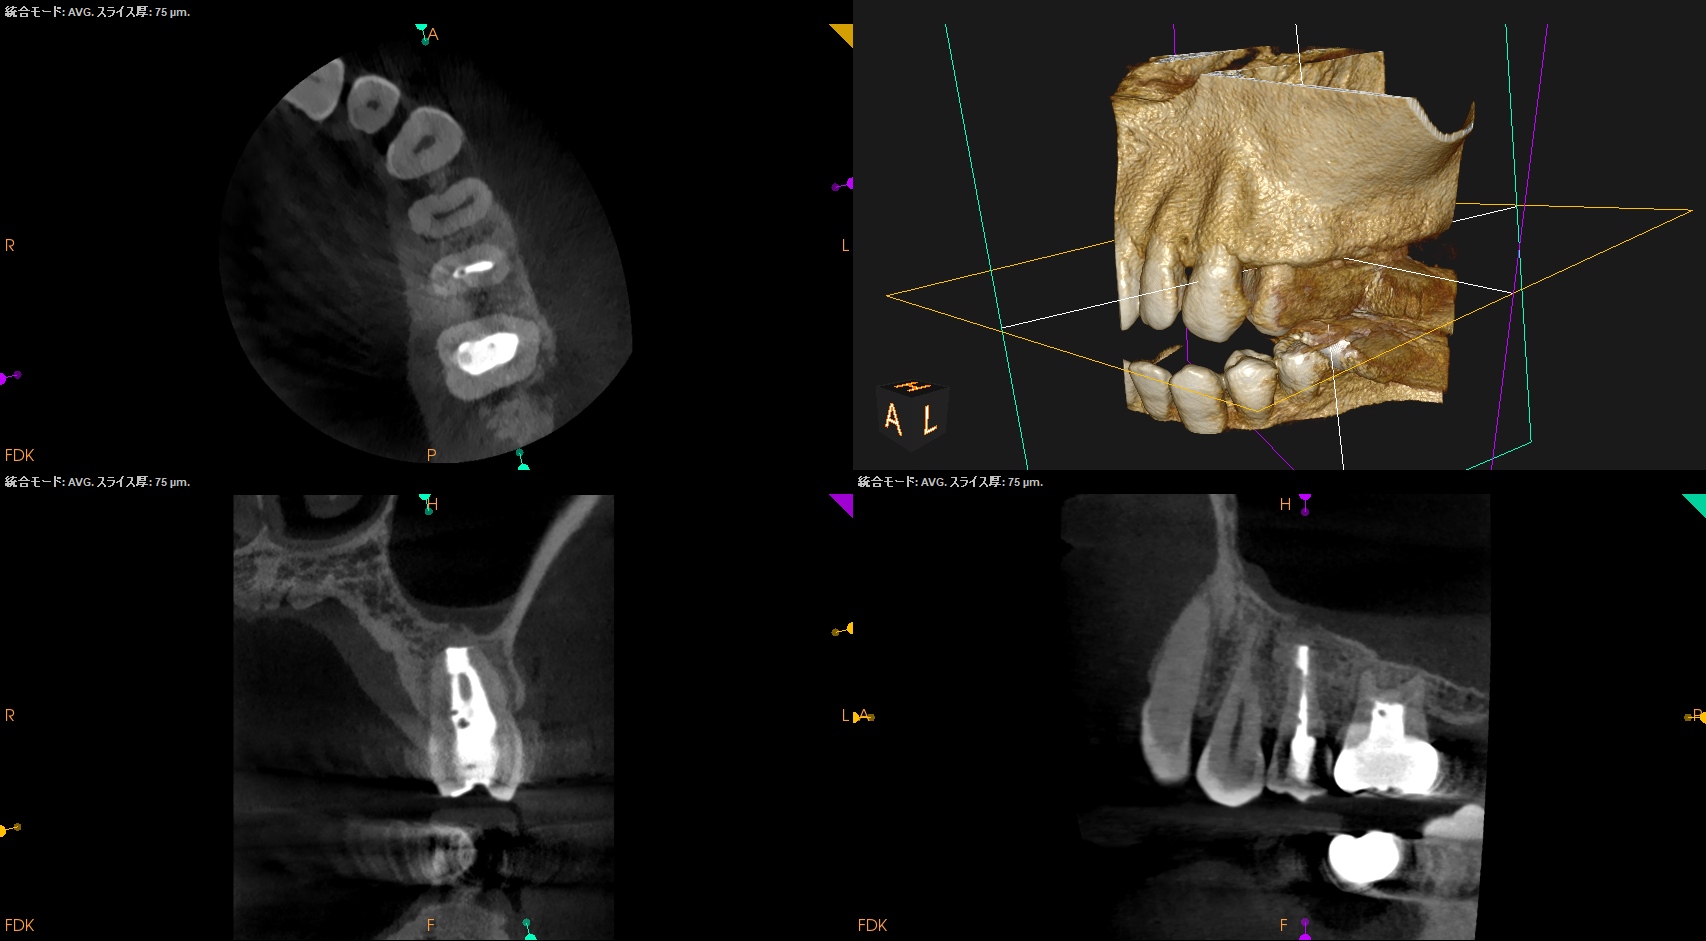

#13 Intentional Replantation 1yr recall(2026.4.10)

1年前と比較した。

歯槽骨の欠損部分は完治した。

打診時のアンキローシス音もない。

ということで、臨床症状もないのでこの日で終診とさせていただいた。